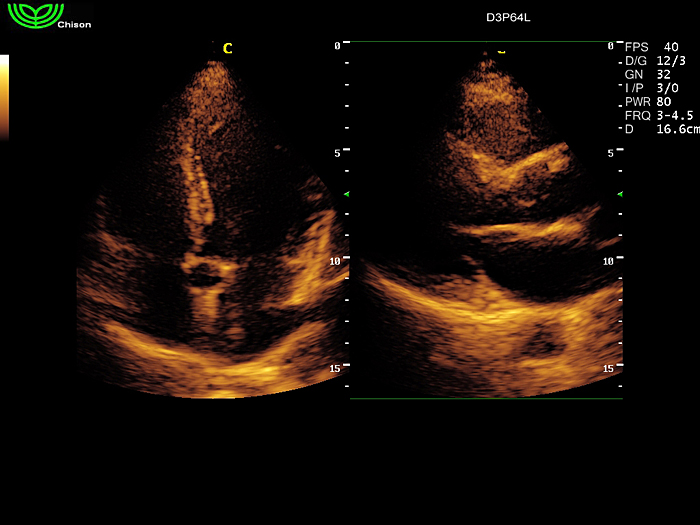

D3P64L 3.0МГц, фазированная решетка.

2.0МГц – 4.4МГц. Применения: кардиология, брюшная полость, акушерство. |